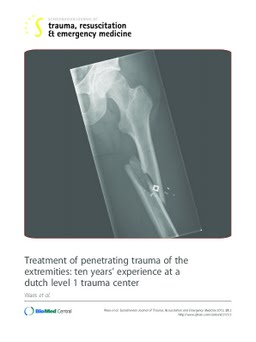

Treatment of penetrating trauma of the extremities: Ten years' experience at a dutch level 1 trauma center

Background: A selective non-operative management (SNOM) has found to be an adequate and safe strategy to assess and treat patients suffering from penetrating trauma of the extremities (PTE). With this SNOM comes a strategy in which adjuvant investigations or interventions are not routinely performed, but based on physical examination only.Methods: All subsequent patients presented with PTE at a Dutch level I trauma center from October 2000 to June 2011 were included in this study. In-hospital and long-term outcome was analysed in the light of assessment of these patients according to the SNOM protocol.Results: A total of 668 patients (88.2% male; 33.8% gunshot wounds) with PTE presented at the Emergency Department of a level 1 traumacenter, of whom 156 were admitted for surgical treatment or observation. Overall, 22 (14%) patients that were admitted underwent exploration of the extremity for vascular injury. After conservative observation, two (1.5%) patients needed an intervention to treat (late onset) vascular complications. Other long-term extremity related complications were loss of function or other deformity (n = 9) due to missed nerve injury, including 2 patients with peroneal nerve injury caused by delayed compartment syndrome treatment.Conclusion: A SNOM protocol for initial assessment and treatment of PTE is feasible and safe. Clinical examination of the injured extremity is a reliable diagnostic 'tool' for excluding vascular injury. Repeated assessments for nerve injuries are important as these are the ones that are frequently missed and result in long-term disability. Level of evidence: II / III, retrospective prognostic observational cohort study Key words Penetrating trauma, extremity, vascular injury, complications.